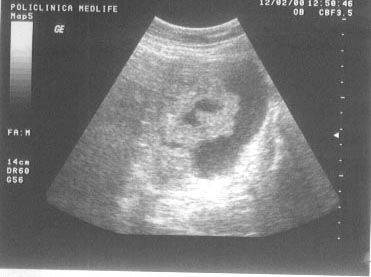

Figura

13. Ovarul st`ng este ]nlocuit de o formaiune complex[, transsonic[ =i

solid[. Partea solid[ ]n proporie de 40%, cu ecostructura hiperecogen[

este dispus[ sub forma de prelungiri papilifere cu contur neregulat =i

prezint[ ]n interior c`teva mici zone transsonice (posibil arii de

necroz[). Aspectul sugereaz[ chistadenocarcinom ovarian.